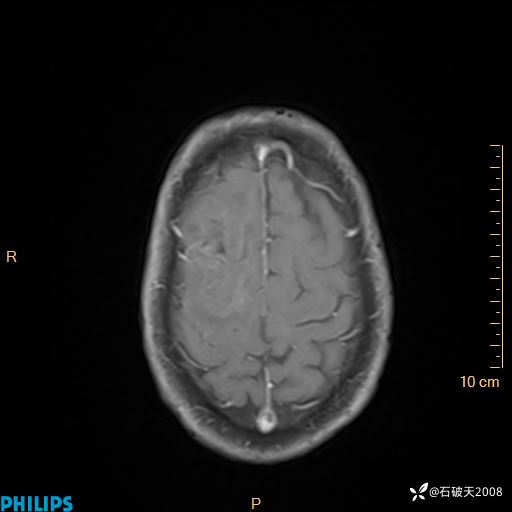

2020.11.14MR

增强轴位